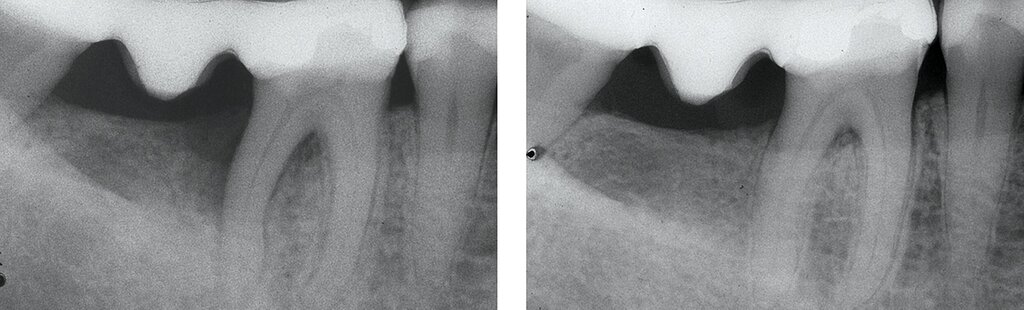

Da der histologische Nachweis einer erfolgreichen Furkationsregeneration kein praktikabler Endpunkt für kontrollierte klinische Studien ist, dienen Veränderungen bei direkten Knochenmessungen (offene Messungen: horizontales Knochensondierungsniveau bei der Operation und während eines „Re-entry“-Eingriffs) als primäre Ergebnisvariablen zur Bewertung des klinischen Erfolgs, während geschlossene Messungen wie der klinische Attachmentgewinn (horizontales/vertikales Attachmentniveau (CAL)), die Reduktion der Taschensondierungstiefe (TST) und röntgenologische Beurteilungen als sekundäre Zielparameter dienen können [Machtei, 1997]. Zu den von den Patienten berichteten Ergebnissen nach einer regenerativen Furkationschirurgie können postoperative Schmerzen, die Komplikationsrate, der wahrgenommene Nutzen und die Veränderung der Lebensqualität gehören.

Ein adäquater Zugang zum Operationsbereich und auch für die zukünftigen Mundhygienemaßnahmen ist äußerst wichtig. Molaren mit Grad-II-Furkationsdefekten (mandibulär und bukkal maxillär) sind Kandidaten, die für ein regeneratives Verfahren infrage kommen. Basierend auf der verfügbaren Evidenz sind interdentale Grad-II-Furkationsdefekte an Oberkiefermolaren deutlich weniger geeignet, höchstwahrscheinlich aufgrund des eingeschränkten Zugangs. Weitere lokale Charakteristika können Auswirkungen auf die Ergebnisse der regenerativen Furkationschirurgie haben. Zum Beispiel können ein dickerer Phänotyp und das Fehlen einer Weichgeweberezession die Heilung nach GTR-Verfahren positiv beeinflussen. Günstigere Ergebnisse sind an Stellen zu erwarten, an denen das verbleibende approximale Knochenniveau koronal zum Eingang beziehungsweise zum Dach des Furkationsdefekts liegt, verglichen mit solchen, bei denen das approximale Knochenniveau auf der Höhe oder apikal des Furkationseingangs liegt. Ein enger interradikulärer Abstand kann eine gründliche Defektinstrumentierung beeinträchtigen. Das Vorhandensein einer Wurzelkanalfüllung ist nicht per se eine Kontraindikation für die Furkationsregeneration – vorausgesetzt, es gibt keine Anzeichen für apikale pathologische Veränderungen.